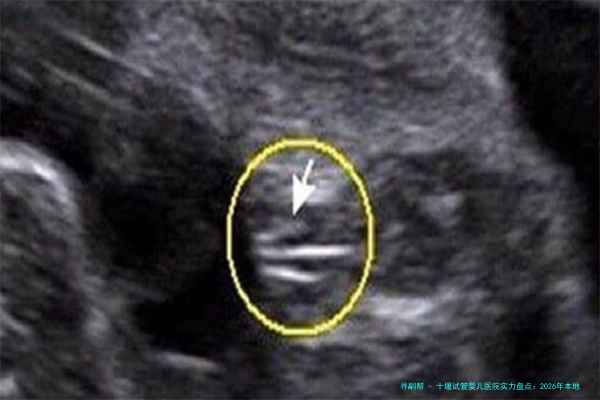

配备:引入了的胚胎实践室设备,如时间差胚胎监测系统(Time-lapse)、前沿的显微操作仪和净化空气系统,为胚胎培养提供了稳定优越的环境。

设备:配备了先进的全自动化精液剖析系统玻璃化冷冻设备用于胚胎和冻卵,以极高精度的检测平台。

配备:拥有新一代的胚胎培育箱激光破膜仪等,用于辅助孵化,提高胚胎着床潜在能力。